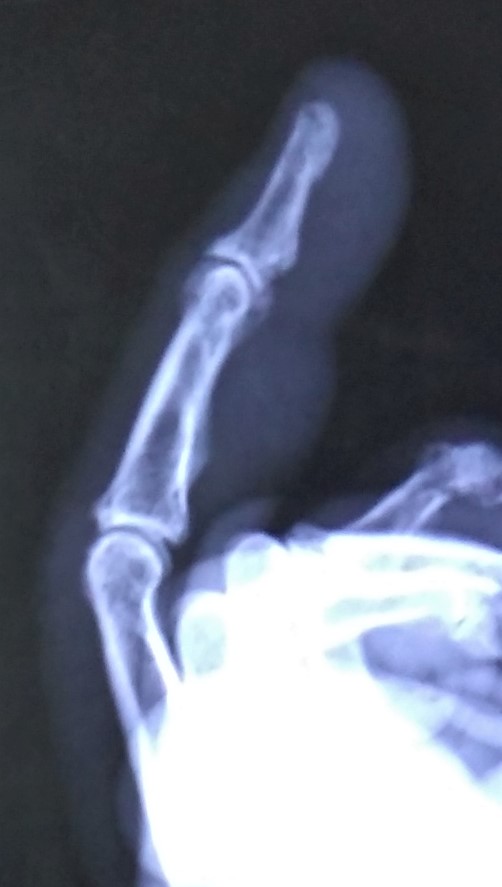

We made it to the clinic a little past 6:45 pm. An x-ray of my finger revealed it was dislocated. I was glad I did not need stitches for my cheek injury.

After trying twice to reset my finger, they splinted it, told me to keep it iced and made an appointment at Teton Orthopedic the next day for further treatment.

The next morning I was told the hand specialist at Teton Orthopedic had the day off. However, when she saw the x-ray, she made a special trip to the office. She was able to pop it in place to my immediate relief! I was then sent to get a more permanent splint. Shortly after noon we were finished!